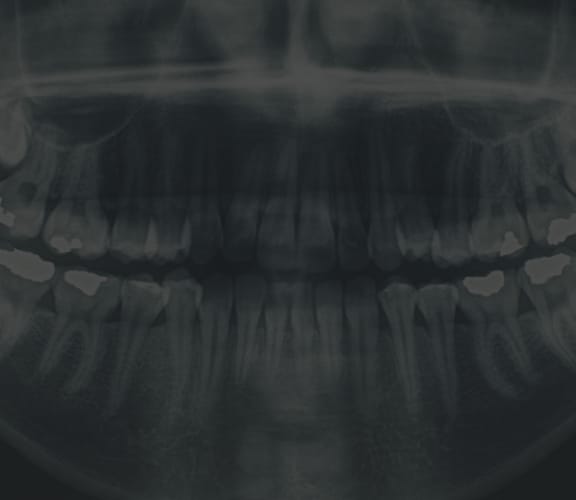

The inside of the mouth is normally lined with a special type of skin (mucosa) that is smooth and coral pink in color. Any alteration in this appearance could be a warning sign for a pathological process. The most serious of these is oral cancer.

These changes can be detected on the lips, cheeks, palate, and gum tissue around the teeth, tongue, face and/or neck. Pain does not always occur with pathology, and curiously, is not often associated with oral cancer. However, any patient with facial and/or oral pain without an obvious cause or reason may also be at risk for oral cancer. We would recommend performing an oral cancer self-examination monthly and remember that your mouth is one of your body's most important warning systems. Do not ignore suspicious lumps or sores. Please contact us so we may help.